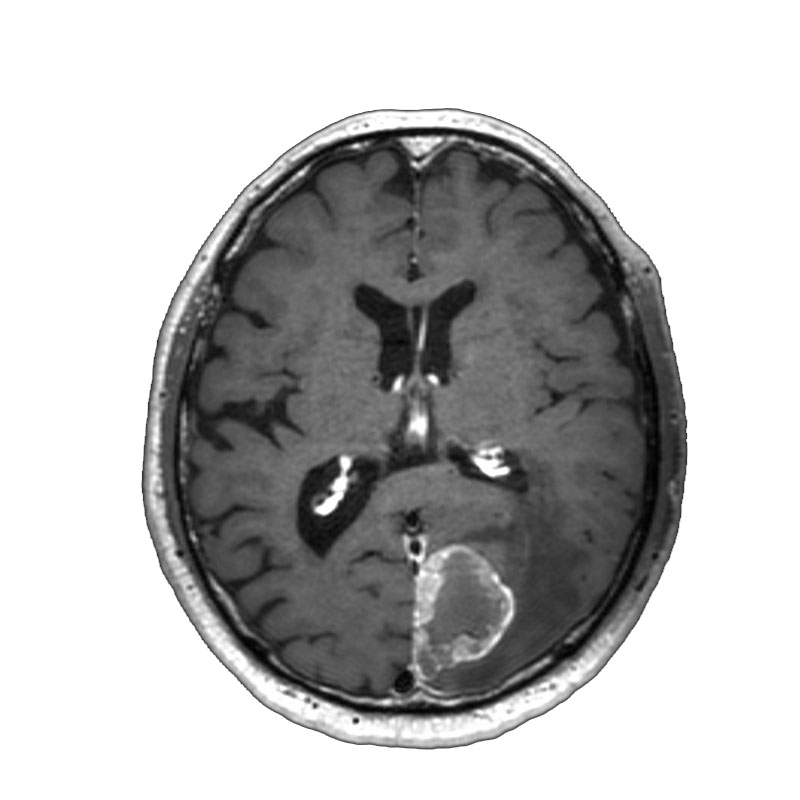

脳動静脈奇形

血管塞栓術

松田/濵田/元永